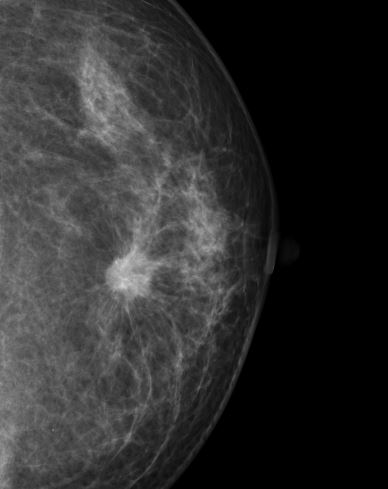

マンモグラフィは、乳房専用のX線検査で、乳がんやその他の乳房の病変を早期に発見するための画像診断法です。乳房を上下または斜め方向から圧迫して、薄く広げた状態でX線を照射し撮影します。圧迫することで乳腺の重なりを減らし、病変を見つけやすくします。また、少ないX線量で鮮明な画像が得られます。撮影時間は数分程度で、左右の乳房をそれぞれ撮影します。

乳房は主に「脂肪」「乳腺」「血管」などの軟らかい組織(軟部組織)で構成されています。これらは密度差が小さいため、通常のX線(胸部レントゲンなどで使うエネルギー)ではコントラスト差が無く、乳腺の中の乳がんを描出することは困難です。そのため、マンモグラフィではあえて低いエネルギーのX線を使って、軟部組織のわずかな吸収差を画像に反映しやすくしています。また、マンモグラフィでは、乳房内のごく小さな病変(1mm以下の石灰化など) も見逃さないように、高解像度の画像を生成できるように設計されています。

マンモグラフィの画像 |